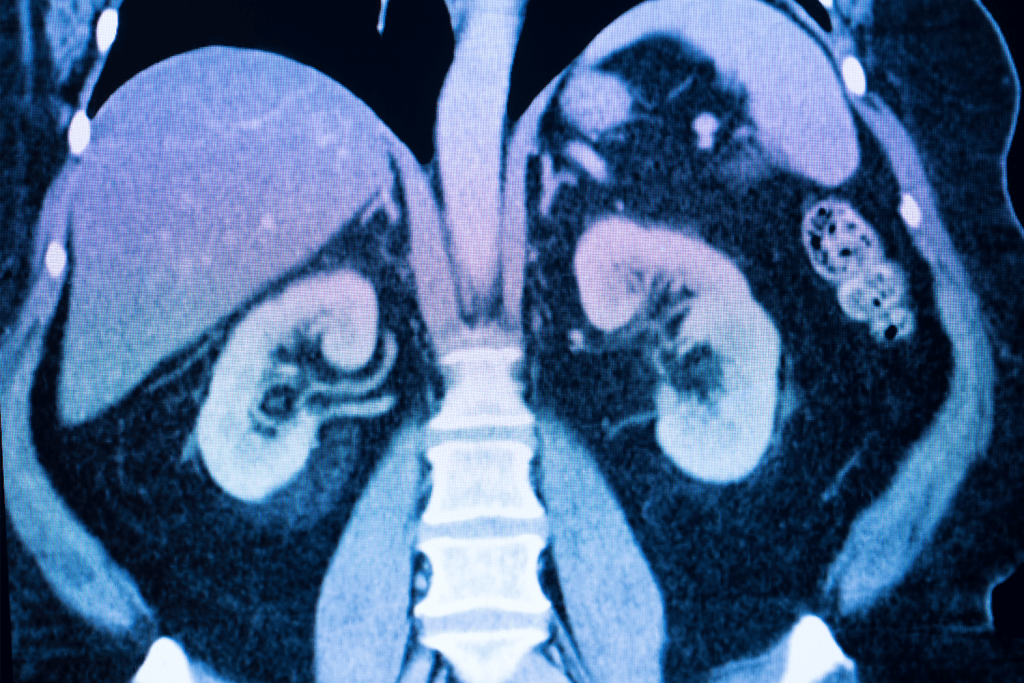

MRI scans of the kidneys give a detailed look at the kidneys’ structure and any problems. They help doctors make accurate diagnoses and plan treatments. This method is great for showing how the kidneys work and any issues they might have.

Detailed Imaging of Kidney Structure and Function

Kidney MRI scans take high-quality pictures of the kidneys. Doctors can see how they look and work. This is ketoor spotting problems and understanding how serious they are.

Detection Capabilities for Tumors, Cysts, and Vascular Anomalies

Kidney MRI scans are great at finding different kinds of problems, like tumors, cysts, and blood vessel issues. The high sensitivity of MRI makes it a top choice for finding kidney diseases. Early detection means doctors can act fast.